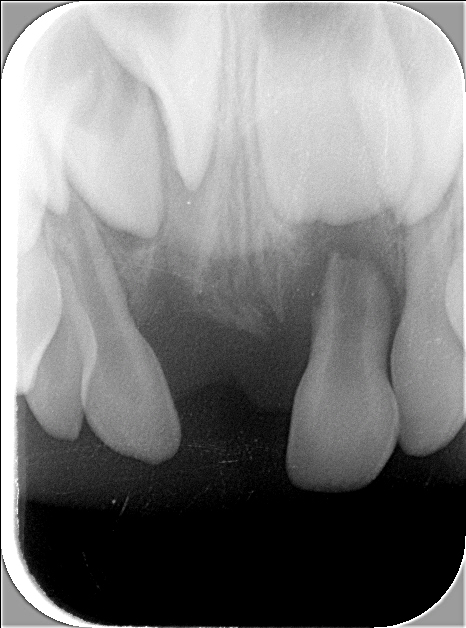

Röntgenbild 1

Dieses zeigt das Standard-Oberkiefer-Front-Röntgenbild, das gemacht wurde, um die Entzündung des linken mittleren Schneidezahnes darzustellen (schwarze Pfeile). Ebenfalls ist darauf zusehen, dass der Zahn 11 (mittlerer bleibender Schneidezahn) noch etwas «verdreht» im Knochen steht, sowie der vermutete überzählige Zahn 12'.

Röntgenbild der Oberkiefer-Front